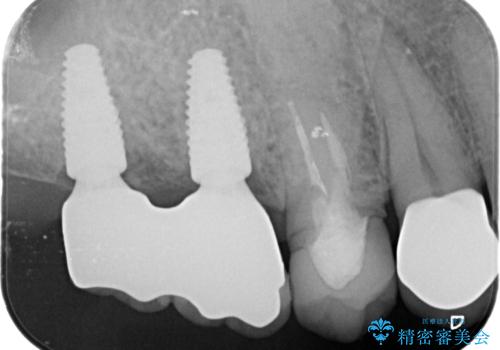

人工歯根であるインプラントを埋入することで奥歯でまたしっかりと噛める咬合機能を回復します。

- 88万円(インプラント×2・仮歯×2・チタンカスタムアバットメント×2・ジルコニアクラウン×2)費用は治療当時の料金となります

またしっかりと噛めるようになり、食事を楽しめるようになった!と喜んでいただくことができました。